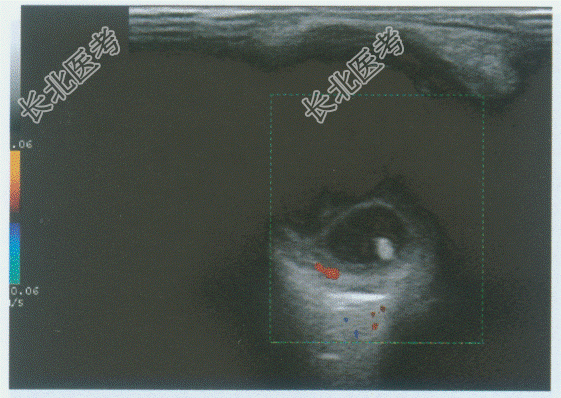

- 单项选择题男性,8岁, 自述左眼视物不清。超声综合描述:左眼玻璃体暗区透声不清亮, 后极部可见椭圆形中强回声光环,内见点状强回声。见下彩图。超声提示:

B、玻璃体内猪囊尾蚴并玻璃体混浊